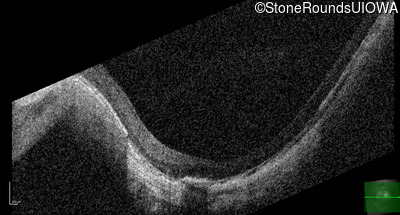

Optical Coherence Tomography - Left - 20/40 +1

Exemplar / OCT Stack

OCT Stack